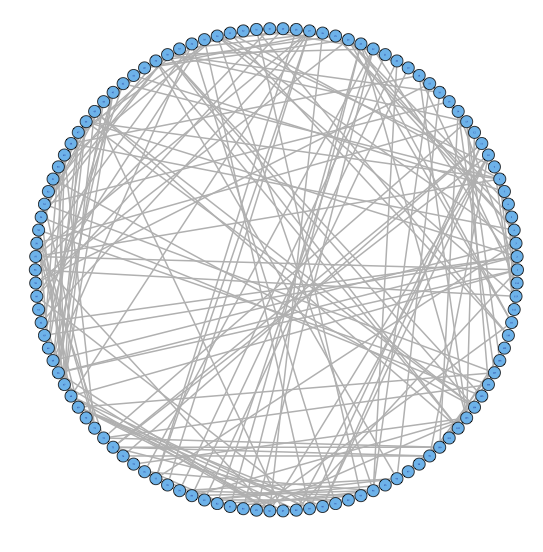

2.2 Challenge I: Two Levels of Network Variability

For our two-level problem (1.1.1), we must account for two sources of network variability when conducting population inference: (i) variability between subjects within a group and (ii) variability of the network selection procedure within a single subject. To see this, let us study a real multi-subject fMRI example. In Figure 2, we show estimated functional brain networks for subjects from the UCLA fMRI ABIDE data set INDI (2013). We describe the details of this data set, our pre-processing, and brain parcellation later in the Case Study in Section 5. In the top and middle panels, we estimate brain networks for each subject using graph selection methods for Gaussian graphical models (see Section 3.1 for details) and plot these as circle graphs to easily visualize network differences. It is clear that there are not only differences between autistic subjects and control subjects, but there is also large heterogeneity across subjects within each group. This is well-known in the neuroimaging literature (Milham et al., 2012; Nielsen et al., 2013), and makes finding statistically significant differences between subject groups much more challenging.

Less well studied in neuroimaging, is the second source of variability which arises from estimating networks for each subject instead of directly observing the networks. In the bottom panel of Figure 2, we re-estimate brain networks for a single control subject with bootstrap resampled data. It is clear that there is major intra-subject variability arising from our graph selection procedure. Indeed in neuroimaging, test–re-test studies which conduct brain imaging on the same subject in repeated sessions have shown high variability in the subject’s estimated brain networks (Wang et al., 2011). This also motivates the necessity of using a two-level model like (1.1.1) for population network inference as opposed to the one-level model and test statistics of the standard procedure.